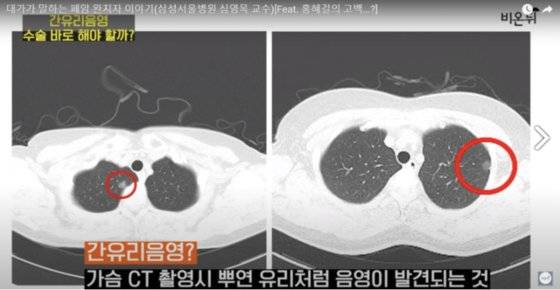

홍씨는 팔에 링거를 꼽고 입원복을 입은 채 카메라 앞에 등장해 “얼마 전, 폐암 직전 단계인 간유리음영을 앓고 있다는 말씀을 드렸는데 며칠 전에 수술을 받았다”면서 “(간유리음영의) 위치는 좌상엽이고 저는 구역절제술로 절반 정도 떼어냈다”고 말했다.

그는 해당 질병에 대해 “드문 병이 아니다. 꽤 흔하다. 중년 이후 CT(컴퓨터단층촬영)를 찍게 되면, 최대 100명 중 5명 정도가 양성 소견을 받는다”라며 “말 그대로 불투명한, 뿌연 막, 유리를 말하는 거다. 회색빛을 띄고 있고 물컹물컹한 질감을 갖고 있다”고 설명했다.

그러면서 결절과 비교했을 때 “일단 CT에서 발견되면 거의 대부분 암세포가 나온다”며 “가볍게 보면 안 된다. 암의 씨앗이 된다. 내버려 두면 계속 자라서 암이 될 수 있다”고 했다.

![홍혜걸씨의 폐 CT 촬영 사진. 빨간색 동그라미 부분이 간유리음영. [유튜브채널 '의학채널 비온뒤' 캡처]](https://img1.daumcdn.net/thumb/R658x0.q70/?fname=https://t1.daumcdn.net/news/202204/24/joongang/20220424184032826ynjk.jpg)

홍씨는 의사들도 간유리음영에 대해 최근에서야 알게 됐다고 전했다. 그는 과거 진단 기록을 토대로 “13년 전 로컬 병원에서 CT를 찍었는데, 1.3cm 크기의 간유리음영이 발견됐다”면서 “그런데 그 때 소견은 결핵을 앓은 적이 있어 그 흔적같다며 신경쓰지 말라는 것이었다. 그때는 폐 CT가 나온지 얼마 안 돼 간유리음영에 대한 정확한 가이드라인이 없어서 뭘 어떻게 해야할 지 몰랐던 것”이라고 설명했다.

홍씨는 이후 2019년 건강검진에서 간유리음영 크기가 직경 1.9cm까지 커진 것을 확인했으며, 이후 30년 동안 피웠던 담배를 끊고 제주도로 이사한 뒤 건강 관리를 시작했다고 전했다.

그러나 이후 최근 검진에서 간유리음영 크기가 더 커지고 경화한 것을 확인, 수술을 결정했다는 설명이다.

홍씨는 그러면서 같은 질병을 앓고 있는 환자들에게 “너무 겁먹지 말라”며 발견시 예후가 좋은 질병이라고 응원했다. 또 “함부로 수술할 건 아니지만 (간유리음영 부분이) 자라는 소견이나 고형화하는 소견이 보이면 수술을 하는 게 좋다”고 조언했다.